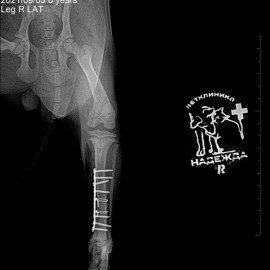

Снимок 1 до операции.